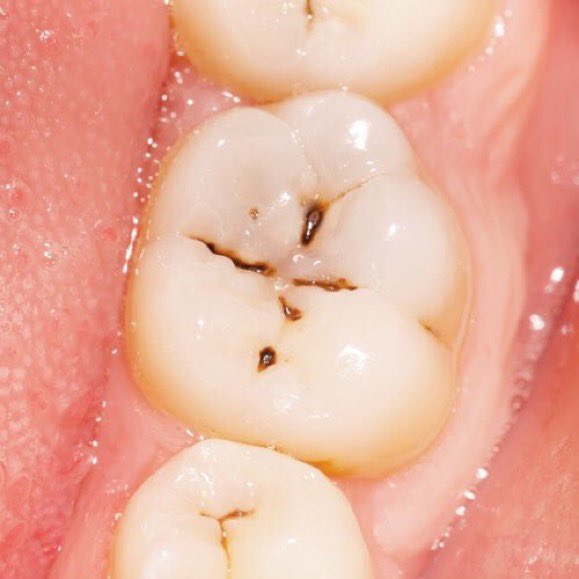

٥/ انواع التسوس:

يمكن تقسيم التسوس للإنسان العادي بتسوس ظاهر أو تسوس بين الأسنان. الاول تراه بعينك حين تنظر في المرآة، والثاني لا يمكن اكتشافه بدون أشعة خاصة وهامة يعملها الطبيب خلال التشخيص والفحص الدوري